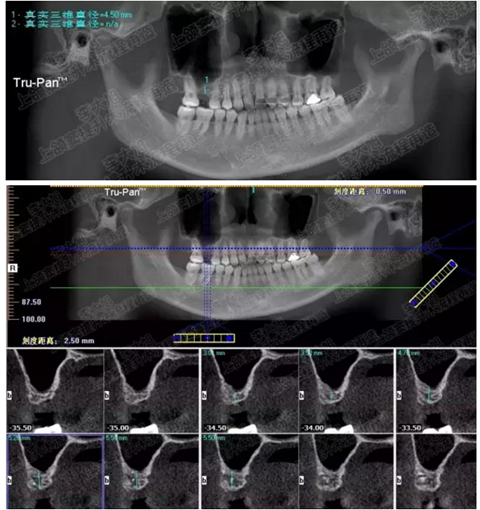

病例一

上頜竇多分隔3mm

05.png

提升8mm

06.png

07.png

修復(fù)時(shí)根尖片

08.png

09.png